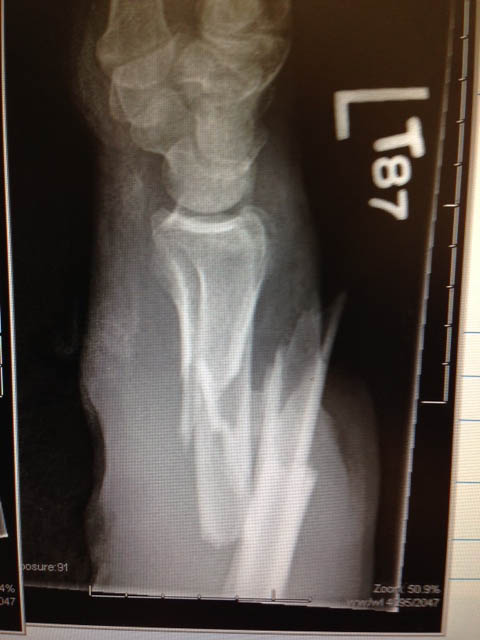

Ness’ arm became entangled in the mill, breaking his arm and severely injuring his pinkie finger. The leather glove stopped the cutter and prevented further damage but by this time Ness could see the bone in his arm had broken the skin.

“It actually went in reverse and started moving my arm and everything out of there,” said Ness. “Then I was in shock because my head was bleeding, my glasses were gone and then my arm is looking pretty bad with both bones sticking right out of my arm and everything.”

The ambulance arrived shortly and Ness was transported to a local hospital, which quickly sent him to a major trauma center in Minneapolis. The doctors set his arm, which was broken in 15 places, and ended up having to amputate the finger. His surgery last five-and-a-half hours.